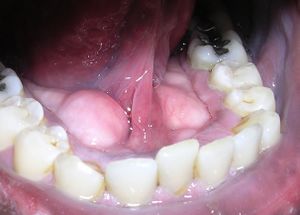

اللّويحة السّنّيّة Dental plaque عبارة عن بيوفيلم متراكم على الأسنان، تتميّز بلونها الأصفر الشاحب.

اكتشاف تراكم اللويحات

اكتشاف اللويحات عادة ما يتم سريرياً بكواشف اظهار اللويحات. وتحتوي كواشف اظهار اللويحات صبغة تتحول إلى اللون الأحمر الزاهي لبيان تراكم اللويحات.